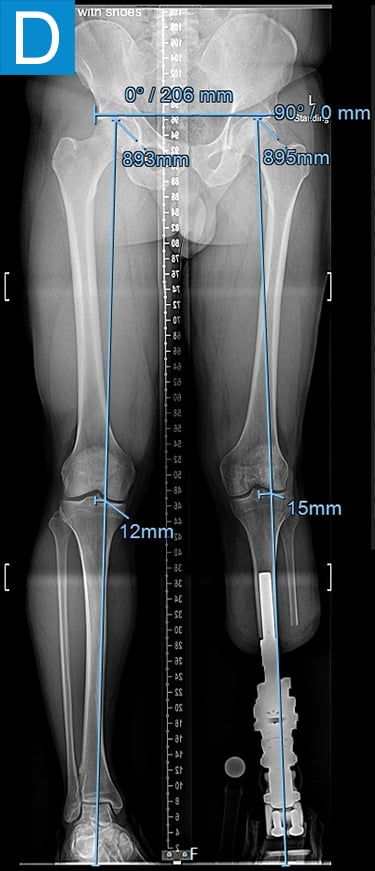

Examination (Figure 1) was notable for a valgus left foot and ankle, with reduced muscle bulk versus the right. His gait was antalgic on the left with minimal knee flexion throughout and no ankle push off (Video 1). Radiographs showed the left leg to be 4 cm shorter than right, with genu valgum, malunion of the lengthened tibia, the recently placed distal tibia fixation, and a ball and socket ankle with short fibula featuring nonunion and malunion at different locations, characteristic of fibular deficiency. He was counseled that a pain-free limb could be provided via reconstructions including hardware removal, distal tibia osteotomy, hindfoot fusion, distal femur osteotomy, and lengthening. He wanted a faster option for painless, high-demand function and asked if he could have tibial osseointegration instead. This was indeed a reasonable option for him. He elected to defer distal femur osteotomy unless the knee remained symptomatic.

Figure 1. Preoperative clinical photos and radiographs. (A) Front and (B) rear views of the patient show a short left leg with foot and ankle valgus and genu valgum and a left calf with reduced musculature. (C) Standing coronal and (D) lateral tibia radiographs depict the prior distal tibia lengthening with fibula nonunion, ankle fracture with fixation, ball and socket ankle, and short fibula. Also note the genu valgum.

Figure 2. Postoperative clinical photos and radiographs. (A) Front and (B) rear views show the patient standing with the osseointegrated tibia prosthesis. (C) Photo shows stable and healthy skin at portal site to be, although slightly dry due to the winter weather. The gold-colored metal is part of the permanent transcutaneous implant; the shiny silver-colored metal beneath the gold is part of the clinician-removable prosthesis connector, and the matte silver metal beneath features a screw at the front, by which the patient secures the prosthesis. (D) Standing coronal radiograph depicts residual genu valgum in the osseointegrated leg. (E) Lateral radiograph of the osseointegrated tibia. (F) Coronal radiograph of the left knee shows the distal femur osteotomy. (G) Final coronal radiograph after distal femur plate and screw removal shows well-aligned left leg with osseointegrated prosthesis.